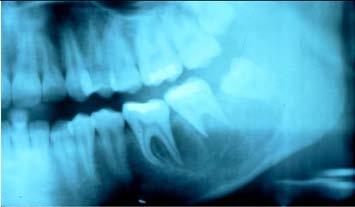

Aneurysmal Bone Cyst

you can see that there is kind of a

multilocular radiolucency in this particular area

✎ There’s a radiolucency involving the second molar

that’s going as far anterior as the first molar and back

to the third molar

✎ There is a little bit of spiking root resorption and

that’s one of the signs that we associate with

malignancy

✎ It’s a little bit ill-defined ~ hard to say exactly

where it begins and ends